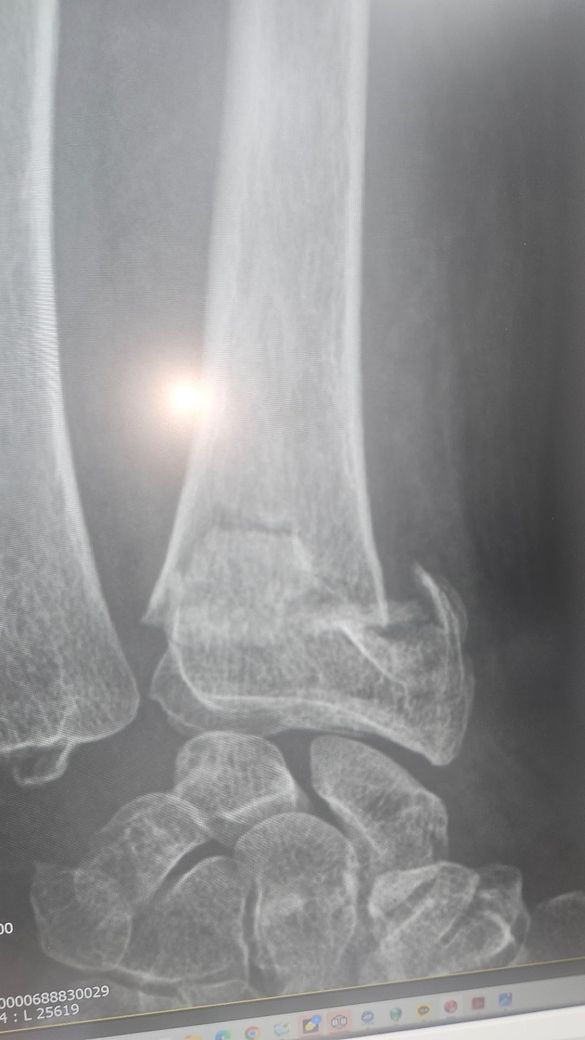

• 2번 째 사진

엑스레이상 골절부위의 어긋남이 심한편이라 병원에서 수술을 권한걸로 보입니다. 현재사용중인 탈부착형 보조기는 세척과 치료는 용이하나 86세 고령환자의 불안정한 골절을 고정하기엔 힘이 부족할수 있습니다. 처방된 약은 단순 진통제가 아니라염증과 붓기완화 목적도 있으므로 임의 중단은 피하는게 좋습니다.현재치료비용과 고정의 불확실성을 고려할때 수술이 정 어렵다면 통깁스를 통해 아예 움직임을 제한할수 있게 고정하는 방안을 담당의사와 상의하는걸 추천드립니다. 뼈가 붙지 않은 상태에서 한의원 방문보다 정형외과적 고정이 최우선입니다. 빠른쾌유를 빕니다.

엑스레이상 손목 요골 원위부 골절로 보이며, 고령에서는 정복이 유지되지 않아 변형 유합 위험이 있습니다.

제시된 X-ray와 경과를 종합하면 관절면을 일부 포함한 원위 요골 골절에 전위가 있었고, 정복 후에도 고정이 안정적으로 유지되지 않는 흐름입니다. 특히 반깁스를 반복하면서 정렬이 흔들린다는 점은 비수술 치료의 핵심 조건인 “정복 유지”가 실패할 위험 신호입니다. 이런 경우 시간이 지나면 부정유합으로 이어지고, 손목 변형과 회전 제한, 악력 저하가 남을 가능성이 높습니다.

지금 제시된 영상은 전형적인 원위 요골 골절로 보이며, 관절면을 일부 침범하면서 전위가 동반된 형태 가능성이 있습니다. 고령에서 흔한 골다공증성 골절 양상과 일치합니다. 정복 후 유지가 핵심인데, 현재 사진과 경과 설명상 “정복 유지 안정성”이 충분한지 의문이 있습니다.

비수술 치료의 적응은 [전위가 크지 않고, 정복 후에도 정렬이 유지되는 경우]입니다. 반면 다음 상황이면 수술을 고려하는 것이 일반적입니다. 관절면이 어긋난 경우, 등쪽으로 많이 꺾인 경우, 요골 길이 단축이 있는 경우, 그리고 정복 후에도 다시 틀어지는 경우입니다. 현재처럼 반깁스를 자주 풀고 다시 고정하면서 정렬이 반복적으로 변한다면, 유지 실패 가능성이 높습니다.